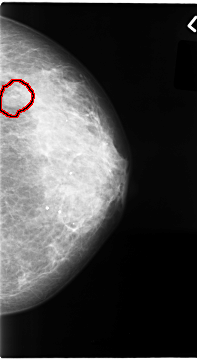

C_0065_1.LEFT_CC

LEFT_CC LINES 4680 PIXELS_PER_LINE 2560 BITS_PER_PIXEL 12 RESOLUTION 50 OVERLAY

FILE: C_0065_1.LEFT_CC.OVERLAY

TOTAL_ABNORMALITIES 1

ABNORMALITY 1

LESION_TYPE MASS SHAPE OVAL MARGINS MICROLOBULATED

ASSESSMENT 4

SUBTLETY 4

PATHOLOGY MALIGNANT

TOTAL_OUTLINES 1

BOUNDARY